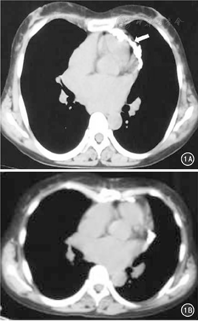

术后34例获随访,随访0.5~10年,平均4.6年。术后3个月复查胸部CT:手术区无心包增生、钙化。随访期间患者无复发。34例基本恢复日常工作、生活。典型病例见图1。